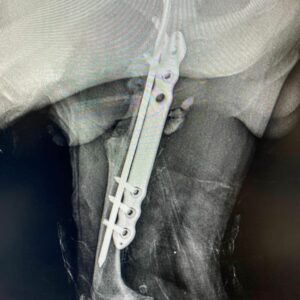

Prezentujemy efekty artrodezy stawu koronowego za pomocą odpowiedniej płytki blokowanej w systemie 5.0 wykonanej w Equi Vet Serwis Dr […]